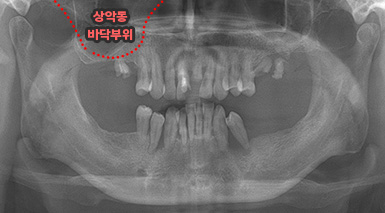

상악동 거상술

상악동 거상술 고난이도 뼈이식술 입니다.

청담네오플란트에서는 상악동 거상술을 비롯한

고난이도 임플란트 시술 노하우가 풍부한 치의학 박사

전문의가 직접 상악동 거상술을 시행합니다

상악동은 윗턱뼈 내부의 구조물로서 개개인에 따라 생김새가 다릅니다.

상악동의 바닥이 잇몸뼈 방향으로 많이 내려온 경우, 임플란트를 식립하기에

잇몸뼈가 부족하게 됩니다. 이러한 경우 상악동 내부로 뼈이식을 하는

상악동 거상술이 필요하게 됩니다.